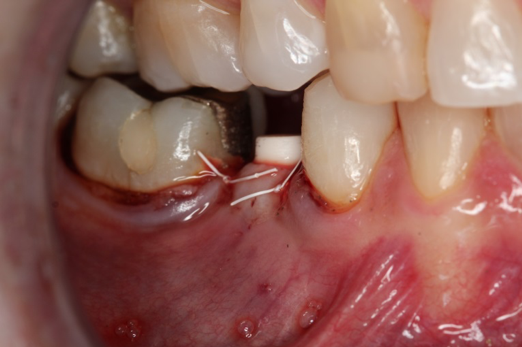

Fig 1. Preoperative surgery.

Figure 1

Fig 2. Extractions and immediate placement.

Figure 2

Figure 1 and Figure 2 depict the preoperative image and subsequent removal of three posterior teeth, immediate placement of zirconia-oxide ceramic dental implants, and soft-tissue augmentation with platelet-rich fibrin (PRF) to enhance the soft-tissue architecture surrounding the ceramic implants. The teeth were removed atraumatically and without suture placement. Because the implants were one-piece in stature (the abutment was incorporated into the implant), the recommendation was to splint the multiple units to minimize the lateral forces from mastication, swallowing, and tongue movement.